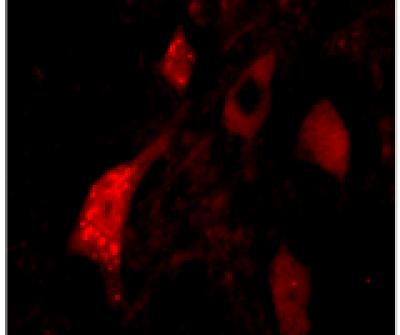

SMA is a devastating motor neuron disease which affects children. It is caused by an abnormal survival motor neuron (SMN) gene, which leads to a reduction of SMN protein levels. The disease is currently incurable, and patients often require prolonged medical care as no effective treatments to alleviate the condition, currently exist.

The research team at Sheffield, led by Professor Mimoun Azzouz, tested whether a novel gene replacement therapy through a single injection was the most efficient way to treat the disease in a group of mice. They found that the injection, which expressed the SMN gene, successfully restored the SMN protein to normal levels and alleviated symptoms in the SMA model.